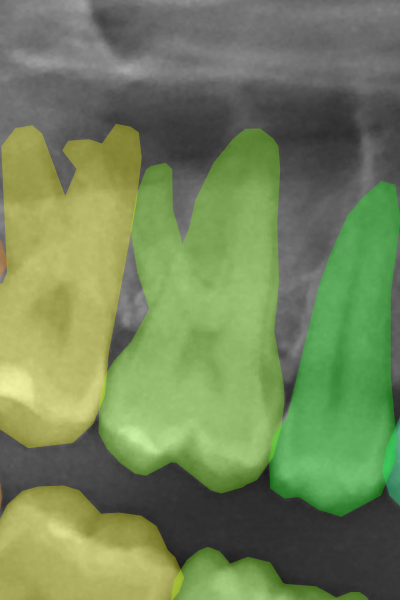

Figure 3 displays corresponding label samples of the aforementioned criteria. We followed the same criteria to label 400 additional images (40 per radiograph category). These images compounded our test set for assessing the neural networks trained at each HITL iteration.

Refer to caption

(a) Implants.

(b) Protheses.

(c) Molar roots.

(d) Restorations.

(e) Appliances.

Figure 3: Label samples of the employed criteria for annotating implants, prostheses, molar roots, restorations, and dental appliances. In general, the labels should be more refined on sharp and well-focused images, while in blurry images, the annotators should rely more on the tooth anatomical structures.